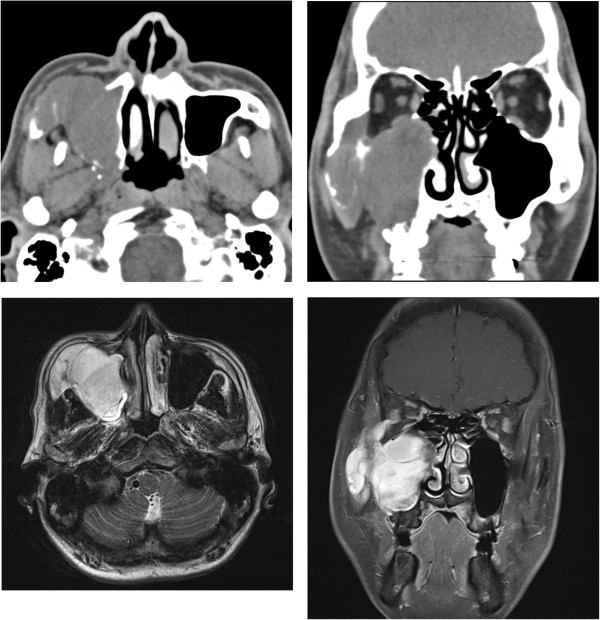

CT, MRI, and 3D-CT examinations of the head and neck regions conducted in April revealed a mass that had invaded the medial, anterior, and posterior walls of the right axillary sinus, reaching the lateral wall of the orbit and the orbital floor, and whose apex was at the anterior aspect of the zygomatic arch up to the anterior surface of the sphenoid and pterygoid bones. No metastasis to the brain was observed (Figure 1). Ultrasound, endoscopy, angiography, and PET-CT conducted to assess distant metastasis revealed no metastasis.

Figure 1

Paranasal CT and MRI findings of maxillary sinus MFH. The figures show a large mass involving the anterior, posterolateral, and medial walls of the right maxillary sinus; inferior and lateral walls of the right orbit; anterior aspect of the right zygomatic arch; right pterygoid bone; and anterior surface of the right sphenoid bone.